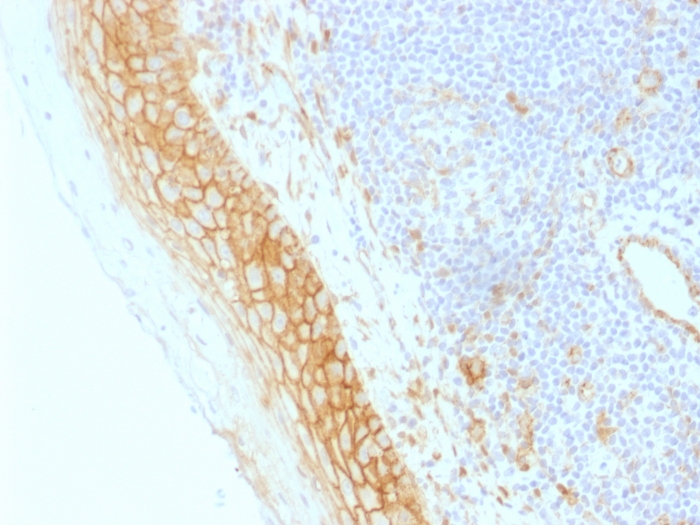

Formalin-fixed, paraffin-embedded human Tonsil stained with Beta-Catenin (p120) Monoclonal Antibody (CTNNB1/1509).

Beta-catenin associates with the cytoplasmic portion of E-cadherin, which is necessary for the function of E-cadherin as an adhesion molecule. In normal tissues, beta-catenin is localized to the membrane of epithelial cells, consistent with its role in the cell adhesion complex. In breast ductal neoplasia, beta-catenin is usually localized in cellular membranes. However, in lobular neoplasia, a marked redistribution of beta-catenin throughout the cytoplasm results in a diffuse cytoplasmic pattern. Immuno-staining of beta-catenin and E-cadherin is helps in the accurate identification of ductal and lobular neoplasms, including a distinction between low-grade ductal carcinoma in situ (DCIS) and lobular carcinoma. Additionally, some rectal and gastric adenocarcinomas demonstrate diffuse cytoplasmic beta-catenin staining and a lack of membranous staining, mimicking the staining pattern observed with lobular breast carcinomas.